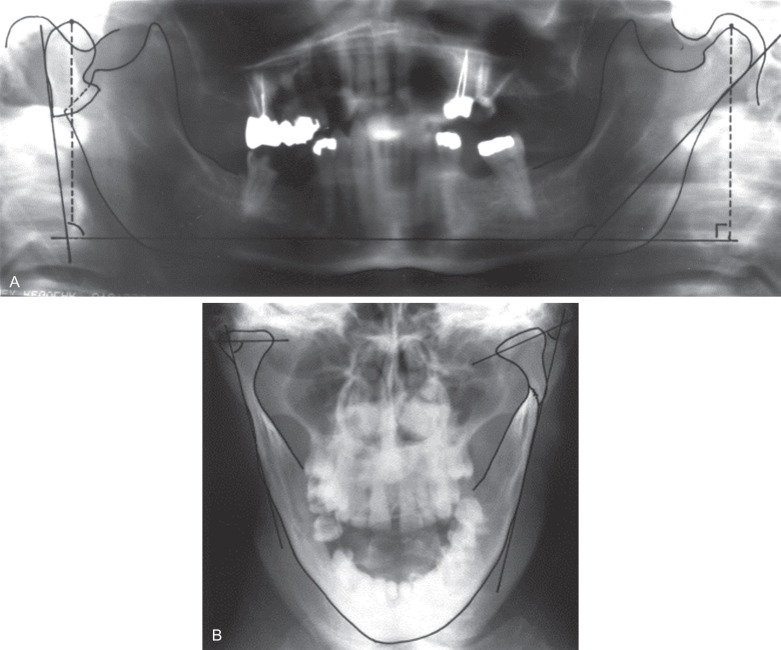

The vast majority of condylar process fractures in adults can be identified using plain radiographs. It is important to get at least two radiographs 90° to the other. For instance, the combination of panoramic and Towne’s projections offer most of what might be needed to prescribe treatment in the vast majority of patients ( Fig. 1.15.5 ). Plain films are not as useful for pediatric condylar process fractures because the bone is less dense, the condylar neck is much shorter, and often the fractures are through the condylar head, which are not revealed well with plain films. On the other hand, if the surgeon routinely treats condylar process fractures in children closed, the need for more detailed imaging (CT) may not be warranted given the need for more radiation to do so.

Displacement. Displacement refers to the relationship of the fractured ends of the bones to one another. Often arbitrarily broken down into mild, moderate and severe displacement, it can be used for fractures throughout the skeleton whereas “dislocation” and “luxation” (see below) can be used only for fractures that involve a joint. The amount of displacement and its direction can be quantified by measuring the angle the condylar process makes with the ramus of the mandible in both the sagittal and coronal planes ( Fig. 1.15.5 ). A fracture that is displaced 90 degrees medially is one that is also dislocated because the articular surfaces will no longer have much contact. The relationship of the fractured ends can be further classified as those with medial and those with lateral override (displacement) of the segments ( Fig. 1.15.7 ).

There are many classification systems in the literature. Classification systems are used for two main purposes. One is to categorize injuries so their treatment may be studied. For this purpose, the classification system must be very complete ( Table 1.15.1 ). Unfortunately, most classification systems used to adequately classify condylar process fractures for purposes of research are complex, cumbersome, and have very little clinical usefulness. The other purpose of a classification system is to help decide between the possibilities for treatment. Such systems do not have to be as complex and the ones that are used the most today by clinicians to classify condylar process fractures are based on the level or anatomic position of the fracture(s) (i.e., head, neck, subcondylar) ( Fig. 1.15.10 ) and the magnitude and direction of displacement of the fragments ( Fig. 1.15.5 ).